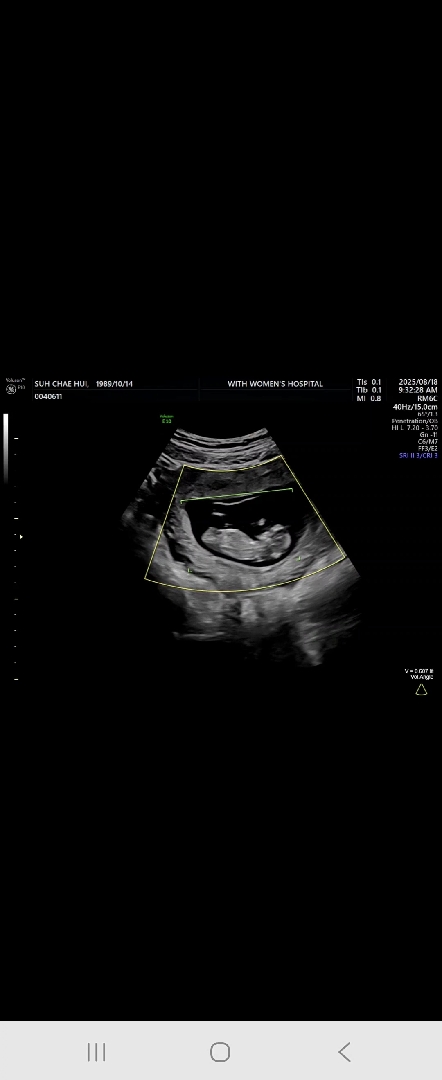

각도법 봐주세요❤️많은참견부탁드려요🫶

딸일까요 아들일까요오❤️